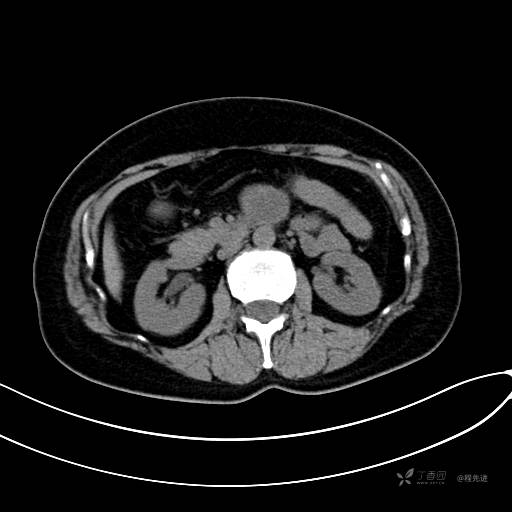

CT增强门脉期